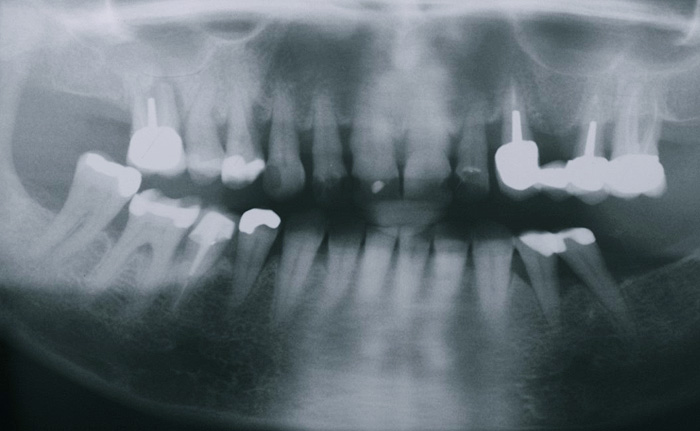

Muss ein Zahn entfernt werden, hinterlässt er eine Lücke. Diese kann mit einer Brücke wieder geschlossen werden. Eine Brücke ist ein zahngetragener, fest zementierter Zahnersatz. Sie besteht in der Regel aus zwei Kronen und einem oder mehreren Zwischengliedern. Bei einer bestehenden Lücke muss immer zwischen einer Brückenversorgung und einer Implantatlösung gut abgeklärt und abgewogen werden.

Gesamtrekonstruktionen

Fehlen in einem Kiefer alle Zähne oder sind die meisten Zähne in einem schlechten, nicht erhaltungswürdigen Zustand, ist es sinnvoll eine Gesamtrekonstruktion anzufertigen. Diese kann sowohl dental als auch implantat-getragen sein. Die Gesamtrekonstruktionen sind zeitlich wie finanziell aufwendig, bestechen aber durch ihre Ästhetik und die Langlebigkeit. Der Vorteil ist, dass viele kleine Arbeiten und Reparaturen in den nächsten Jahren wegfallen werden.